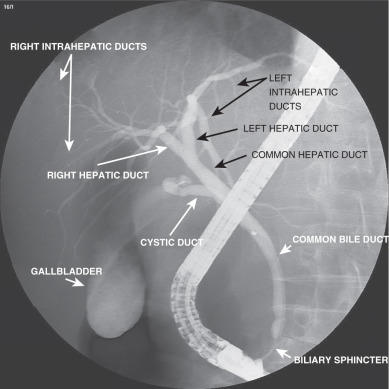

O diagnóstico da CEP normalmente é feito por colangiografia (endoscópica, transparietal ou por ressonância nuclear magnética, apesar da endoscópica ser a preferida). A biópsia hepática é importante no diagnóstico e para avaliar o grau da doença. Exames laboratoriais costumam mostrar aumento da fosfatase alcalina e as transminases quase sempre estão elevadas até 3 a 5 vezes o limite normal. As bilirrubinas podem se elevar à medida que a doença progride. Não há autoanticorpo característico, apesar do p-ANCA (anticorpo anticitoplasma de neutrófilos, padrão perinuclear) e ANA serem comuns (o p-ANCA está presente em 33 a 88% dos portadores de CEP).

| Colangiografia na CEP | ||

| Métodos | endoscópica (CPRE) | desconfortável ao paciente, mas com bons resultados |

| transparietal | invasivo, com risco de complicações e baixa eficácia na CEP | |

| ressonância nuclear magnética | não invasivo e seguro, mas muito caro e disponível em poucos lugares, não permite dilatação ou retirada de material para análise | |

| Achados típicos | estreitamento e irregularidade em vários pontos da via biliar (dentro e fora do fígado), com aspecto de “colar de contas” | |

| dilatação proeminente, massa polipóide e estreitamento progressivo sugerem colangiocarcinoma | ||

Apesar de invasiva, a biópsia hepática pode ser útil no diagnóstico e no prognóstico (avaliação do grau e previsão de complicações). Infelizmente, o grau da doença pode variar bastante em locais diferentes do fígado, prejudicando a eficácia do exame. Em pacientes com diagnóstico bem estabelecido da CEP, por exames laboratoriais e colangiografia, no entanto, a necessidade de realização da biópsia hepática vem sendo rediscutida.